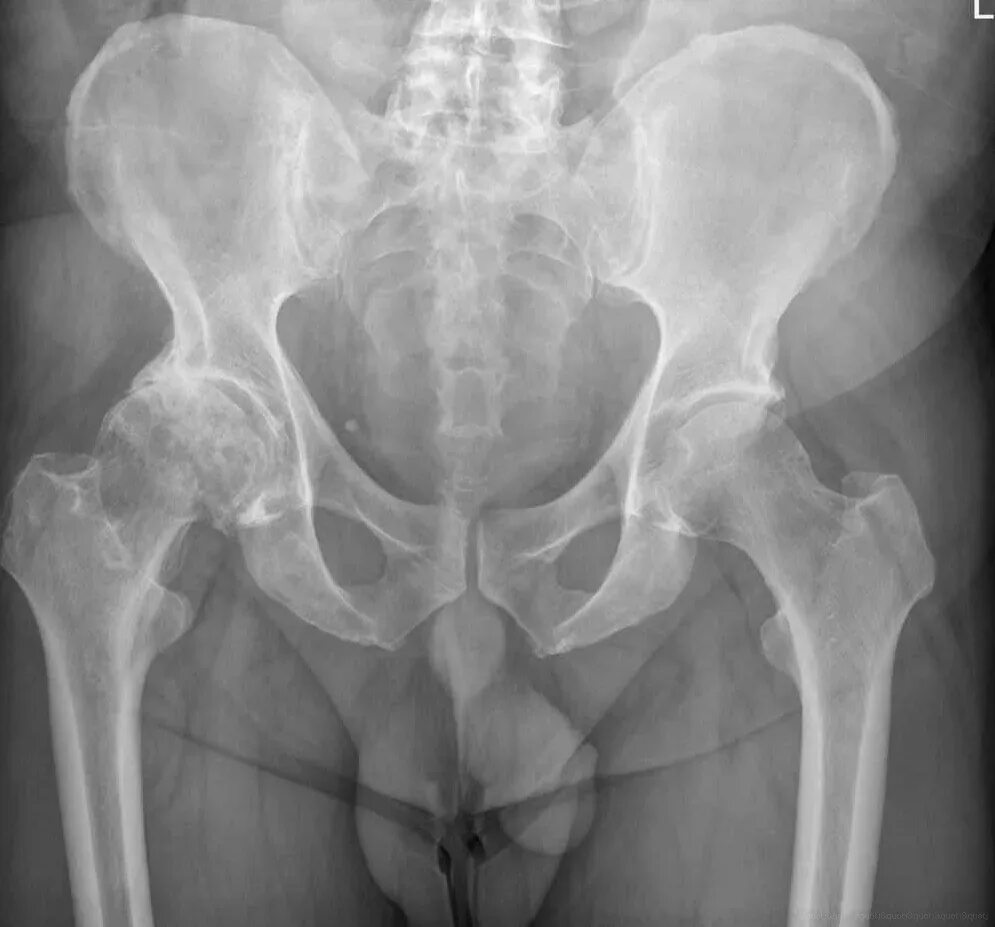

Аваскулярный некроз тазобедренного сустава